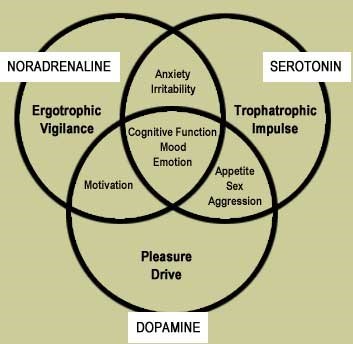

Wie glücklich oder unglücklich wir sind, geht mit vier Botenstoffen sehr eng Hand in Hand. Vor allem der alles entscheidende Freudensaft und Botenstoff zum Aufbau unserer Glücksgefühle Dopamin spielt – in Verbindung mit Noradrenalin

und β-Endorphin – dabei die zentrale Hauptrolle. Aber auch Serotonin ist an

unserem Gluck und Wohlbefinden maßgeblich beteiligt. Dabei sind sie die

stärksten, uns mental (gemütsmäßg-gedanklich) verändernden Wirkstoffe, welche

die Natur in Jahrmillionen zusammengebraut hat.

Wie glücklich oder unglücklich wir sind, geht mit vier Botenstoffen sehr eng Hand in Hand. Vor allem der alles entscheidende Freudensaft und Botenstoff zum Aufbau unserer Glücksgefühle Dopamin spielt – in Verbindung mit Noradrenalin

und β-Endorphin – dabei die zentrale Hauptrolle. Aber auch Serotonin ist an

unserem Gluck und Wohlbefinden maßgeblich beteiligt. Dabei sind sie die

stärksten, uns mental (gemütsmäßg-gedanklich) verändernden Wirkstoffe, welche

die Natur in Jahrmillionen zusammengebraut hat.

Ohne Dopamin, Noradrenalin, Serotonin und β-Endorphin könnte unser Gehirn keine Informationen verarbeiten. Unser individuell unterschiedlicher Botenstoff-Cocktail ist deshalb nicht nur lebensnotwendig, sondern spielt auch die ständig leise Hintergrundmusik bei allem, was wir empfinden, fühlen,

denken (Selbstgesprache), entscheiden und tun oder lassen und uns in einen Zustand versetzt wie: Ich bin (un-)glücklich und (un-)zufrieden.

Überschneidung des Zusammenwirkens von Noradrenalin,

Serotonin und Dopamin (Venn-Diagramm)